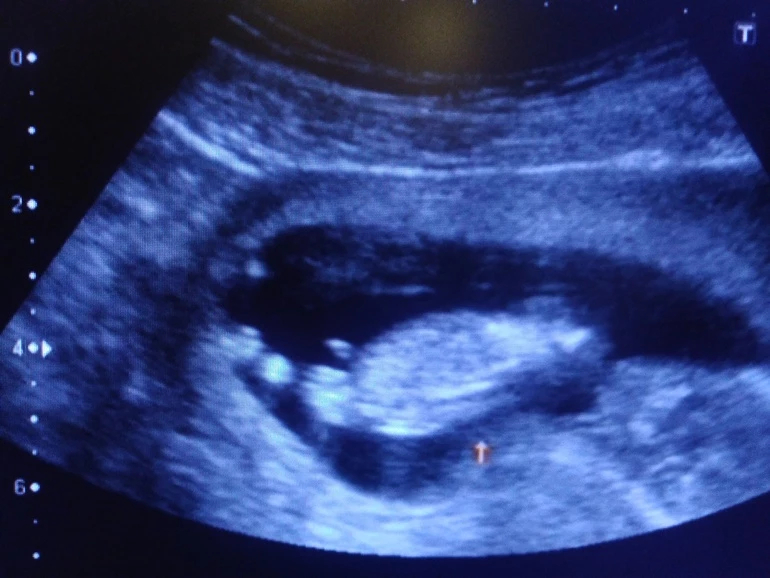

Активный такой мальчуган, еле рассмотрели все! Сказала врач, что редко такое бывает в 12 недель, но "причандал" серьезный, сказала, что сомнений нет-пацан, и показала со всех сторон папину радость))) лежит на спине, пинается ногами и сосёт палец.

Ну вот и позади первый скрининг 12+3, познакомился папа с пузожителем, все хорошо и закрашиваю значок- у нас мальчик!!! Ах, как папа счастлив, и слышать не хотел, что может быть девочка. По ходу сын услышал его мольбы и отрастил в первую очередь "началко", а теперь будет равномерно от "началка" расти))))))))) Почему началко?!- это муж мой так говорит, мол это у него не конец, а началко, он от него вверх и вниз равномерный)))))))))))))) Активный такой мальчуган, еле рассмотрели все! Сказала врач, что редко такое бывает в 12 недель, но "причандал" серьезный, сказала, что сомнений нет-пацан, и показала со всех сторон папину радость))) лежит на спине, пинается ногами и сосёт палец. Я конечно не знаю, что бы там не говорили за кишечник, но я со вчерашнего дня слышу возню именно в одном месте, уровень широкой резинки леггинсов, именно очень похоже на шевелюшки. Ну вот так и получилось, как я предполагала с самых первых дней, - будет мальчик - это они такие капризные))) не успела // увидеть, а уже кипишу сколько пережила, что в 7 недель казалось, что я уже недель 20 беременная, нервотреп казявоШный ))))))). Но все самое интересное ещё только впереди. А вот и папина гордость